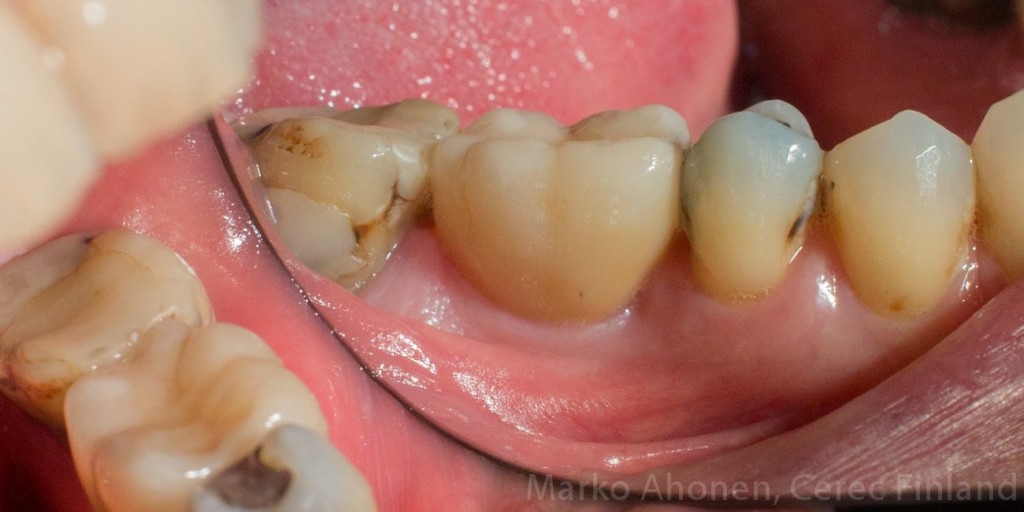

Alkuperäinen tilanne:

IMG_2968 IMG_2972